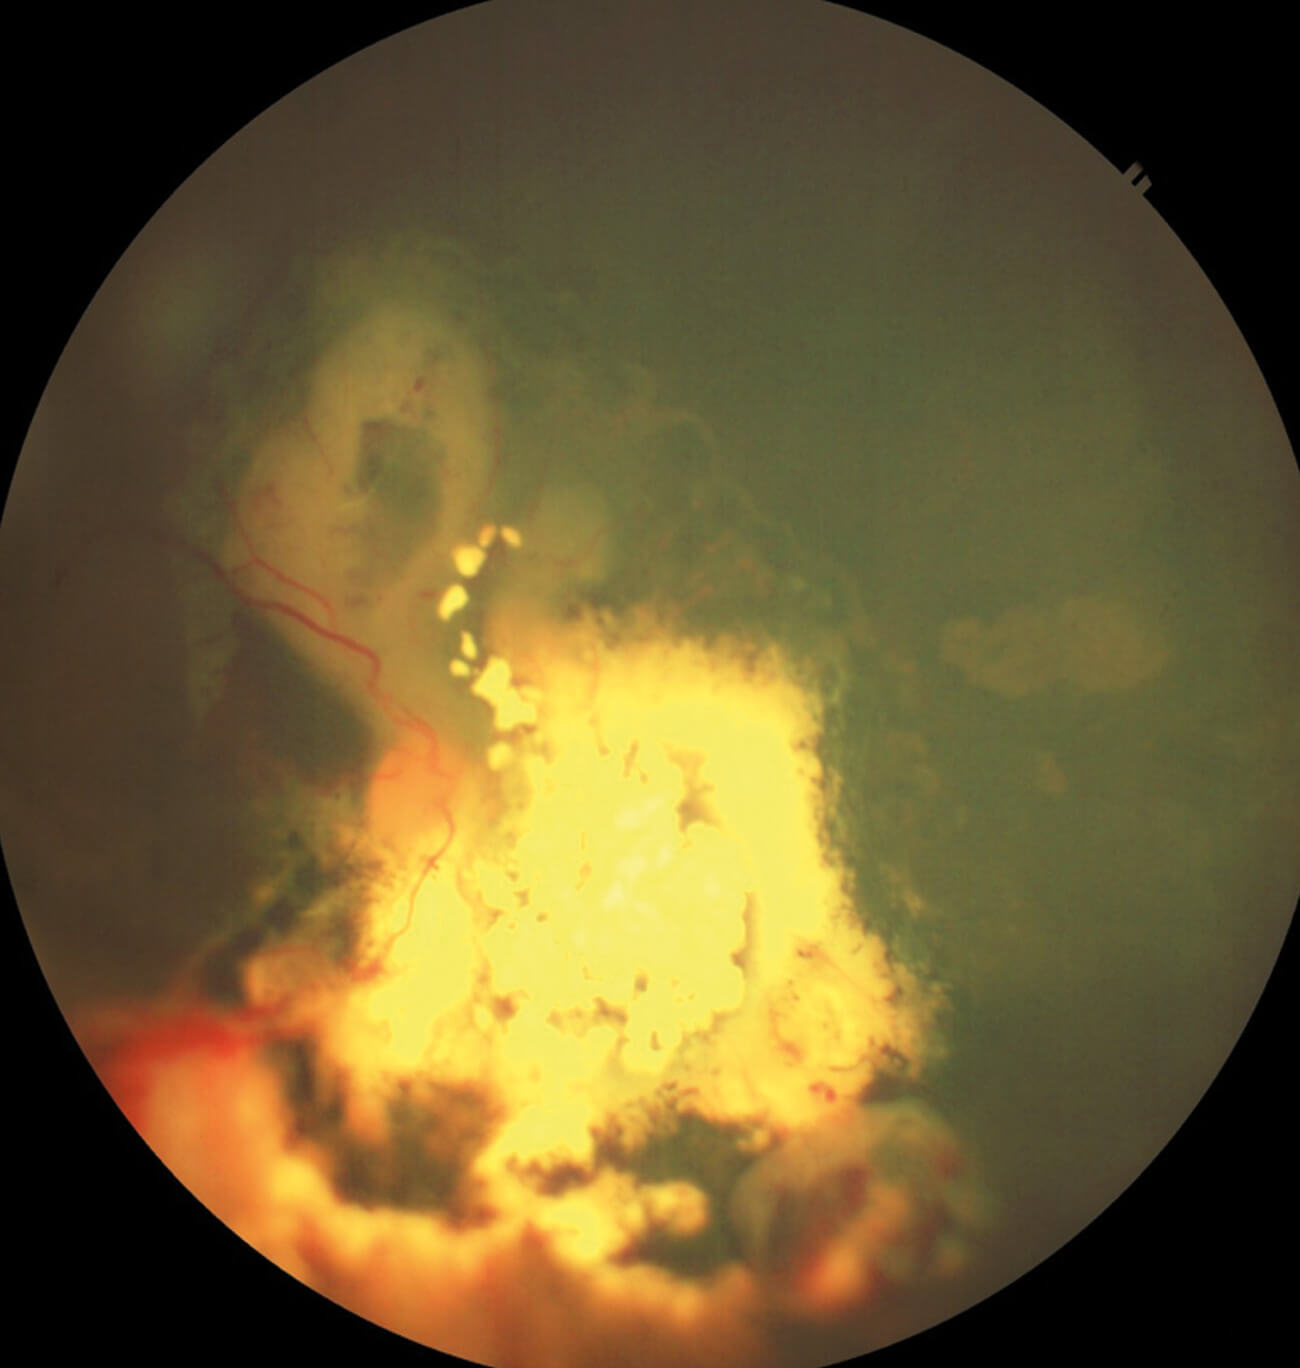

Figure 3: Lesion with localised haemorrhage, scar and different regression patterns.

Over the next two years, the child developed multiple recurrent lesions near the optic disc and macula (Figure 3). Despite 18 cycles of VEC, intravitreal melphalan, and laser therapy, the tumours continued to recur, and second-line chemotherapy was stopped due to toxicity. At this stage, the panel was asked: “What would you do next?”